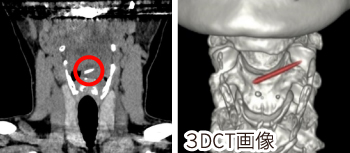

CT撮影(コンピューター断層撮影)

ドーナツ状の機械の穴の中に身体を入れ、放射線を回転させながら当てることで輪切り画像の作成や3D画像の作成ができる検査です。詳細なデータを得られるため病気の精査や、手術前の検査に適しています。

CT

検査結果の例

中耳内に軟部陰影あり

病名

中耳炎